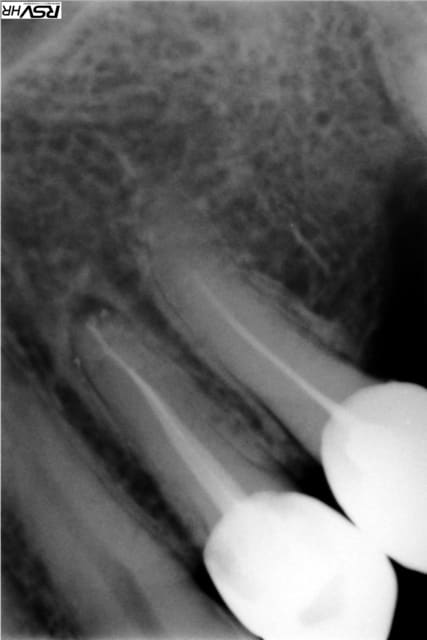

une patiente se présente au mois d'octobre avec plusieurs dents couronnées et des douleurs sur l'une d'elles avec gonflement etc...(ci joint radio préop)

je reprend donc le traitement de la 24 (radio ci jointe), je met la dent d'à coté (asymptomatique) sous surveillance et j'extrait le morceau de racine qui traîne.